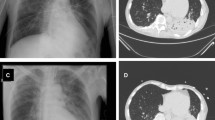

We omitted 23 false positive cases and confirmed 319 cases of E-PRF and 95 cases of L-PRF (Fig. 1).